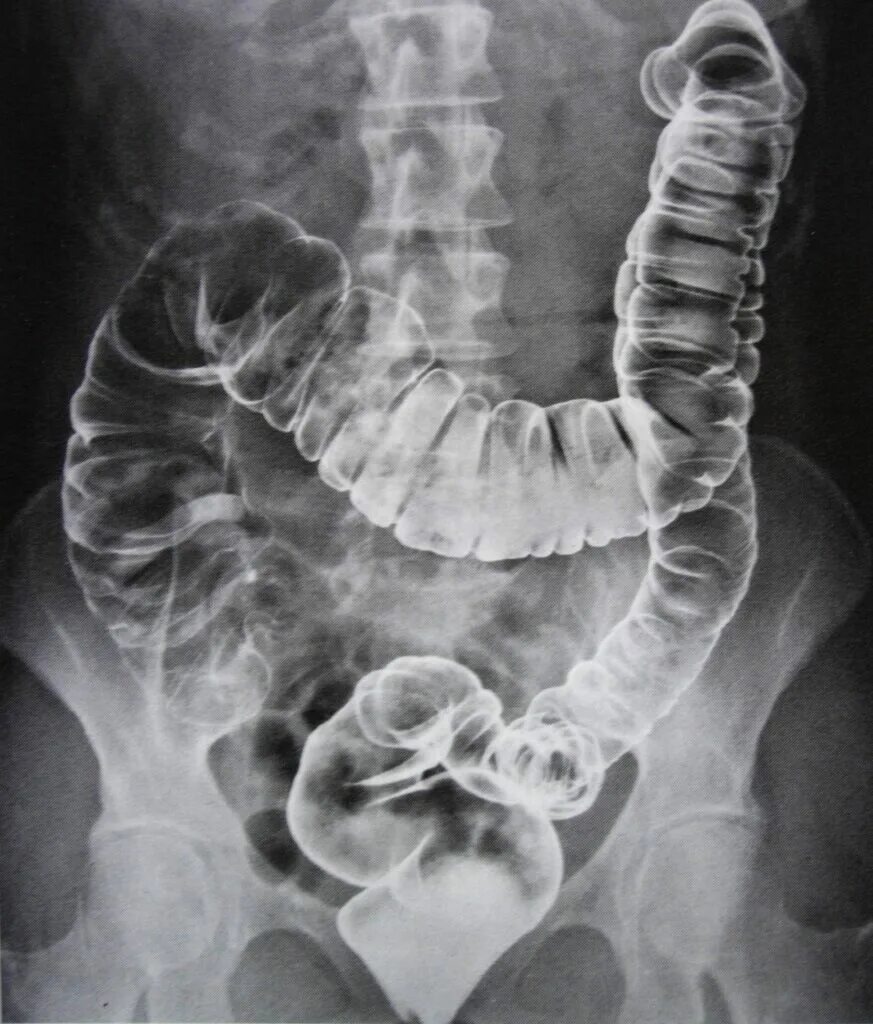

Обследование толстого кишечника